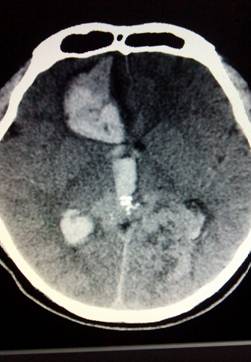

然而当我们把CT片拿给她看,她沉默了……CT显示的是:1.右侧额叶出血破入脑室,出血量约40ml2.蛛网膜下腔积血!